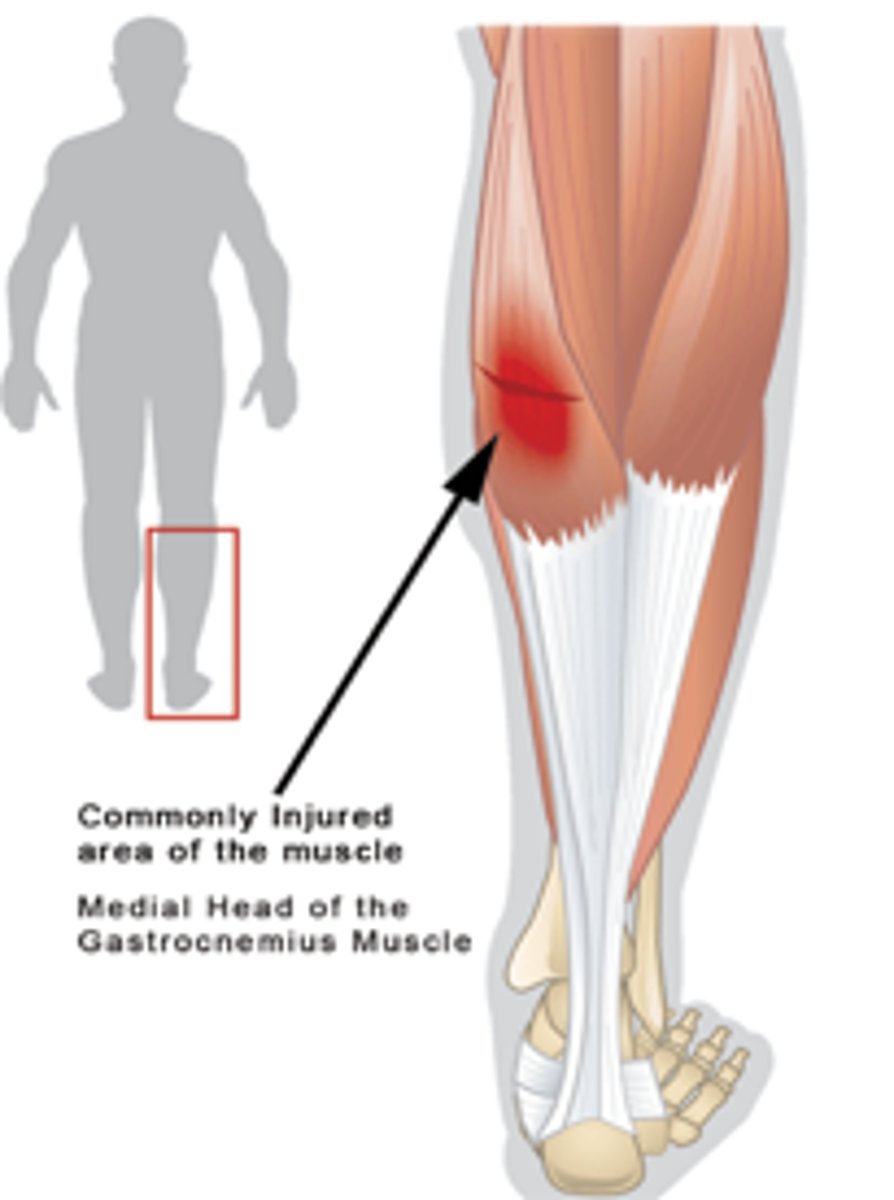

gastrocnemius strain

- Age 20-40

- MOI- sudden overload

pain in upper calf

heel raise increases symptoms

antalgic gait

active and passive DF painful and limited with knee extended

pain on resisted PF

tender mid to upper calf on palpation